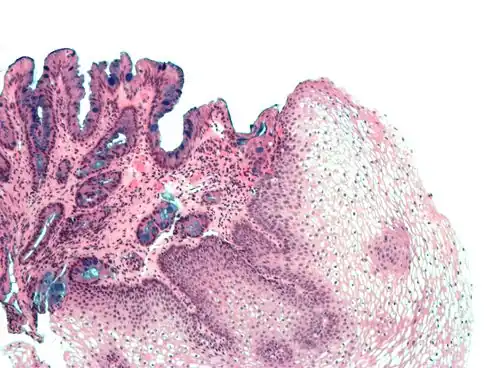

Examples of non-keratinized stratified squamous epithelium include some parts of the lining of oral cavity, pharynx, conjunctiva of eye, upper one-third esophagus, rectum, vulva, and vagina. [3]

Even non-keratinized surfaces, consisting as they do of keratinocytes, have a minor superficial keratinized layer of varying thickness, depending on the age of the epithelium and the damage it has experienced.[4]